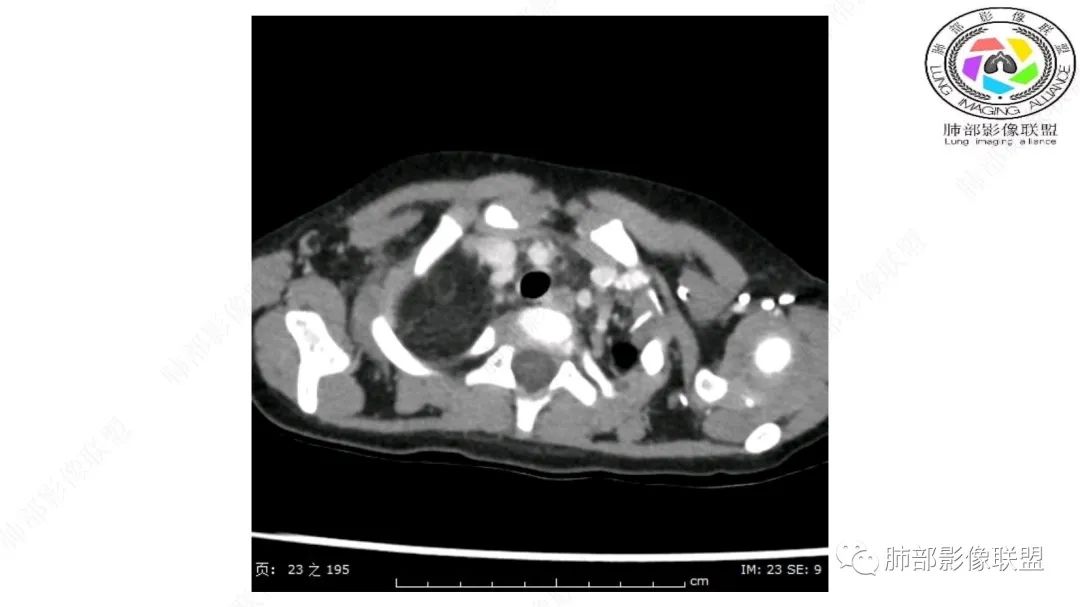

右纵隔团状,密度不均,脂肪密度为主,内可见腺体样组织,类似乳腺,病灶边缘有分叶,与胸腺关系密切,增强后血管穿行。考虑胸腺脂肪瘤(不典型垂乳征),鉴别畸胎瘤。

纵隔畸胎瘤,右前上纵隔团状脂肪密度?粘液样密度为主病变,病灶软边缘有分叶,内可见分隔,增强后血管穿行。3岁。考虑纵隔脂肪母细胞瘤,鉴别畸胎瘤。

跨肺门,包绕肺血管分支,邻近肺组织受压肺不张。

可以看到造影剂进入的丛状结构

密度不均,非纯脂肪成分。斑片状密度略高区域有轻度填充式强化。

病灶属于交界区,主体位于肺内,占位效应明显,前方突入胸壁,胸腺受压变形,胸膜显示欠清楚;病灶包绕上叶肺动脉;似乎有体动脉供血。符合肺内的点:包绕上叶肺动脉分支;符合纵隔的点:前方似乎突入胸壁,与胸腺关系比较密切,但是与上腔静脉的关系提示病灶不支持纵隔来源,前纵隔的常规会将上腔静脉受压后移、外移,这是不符合的。

从这个角度符合肺内的,有一点不太踏实的是:似乎突入前胸壁。

内部血管明显,部分病灶密度增高,单纯脂肪瘤不支持。可惜的是:没有提供CT值:是否强化?如果强化,警惕恶性;胸腺肯定不符合,胸腺会将上腔静脉朝后推移。

2.肺动脉穿行也许是肺内来源最重要支持点!

脂肪母细胞瘤由成熟程度不同的脂肪组织、纤维间隔、黏液基质、小血管丛等间质成分组成,以脂肪组织与黏液样基质为主,其影像学表现取决于上述组织成分。典型的CT和MRI表现为:前后纵隔均可发生,常见于前纵隔;肿块大小不一,直径多在3cm~7cm,密度均匀,CT值呈水样或脂肪密度,脂肪组织密度或信号为主的肿块,其内密度或信号不均匀,可见粗细不一的分隔影,且有结节、片状影,后者可呈轻中度强化;结节状肿瘤包膜完整;弥漫性者包膜不明显,常呈浸润性生长;周围结构为受压和推移改变,可有少量胸腔积液,淋巴结无增大。